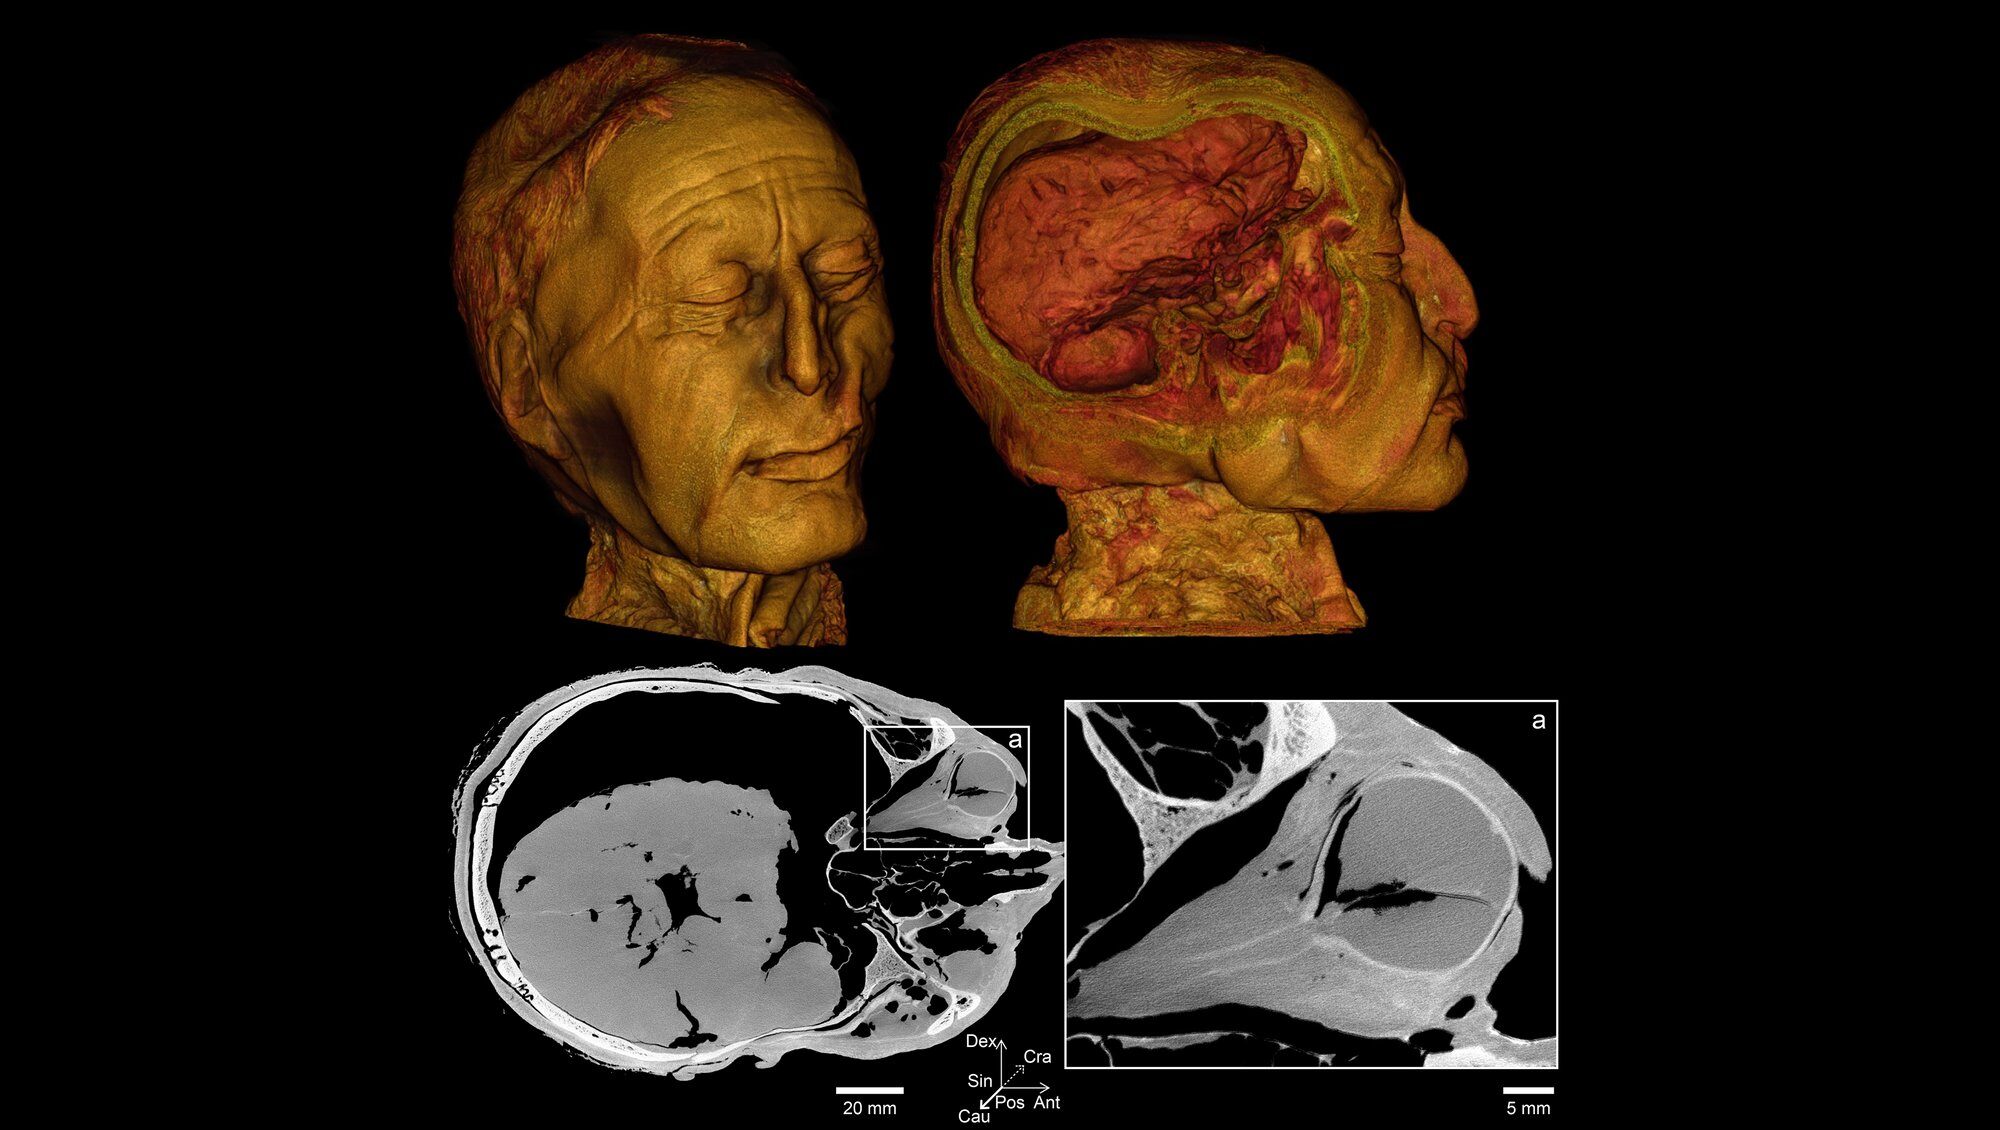

- Eyes: The near-intact condition of one of Tollund Man's eyes allows researchers to study its shape and optic nerve, providing insights into his visual system.

Virtual autopsy of Tollundman's head and brain. With digital dissection, the brain can be viewed - it is well preserved.

The results of the Tollund Man scan using the TESCAN CoreTOM are still being analyzed but promise to enhance our understanding of this Iron Age individual. By studying his teeth, eyes, and other features, researchers may better determine his cause of death, reconstruct his diet and health, and gain insights into his social status.